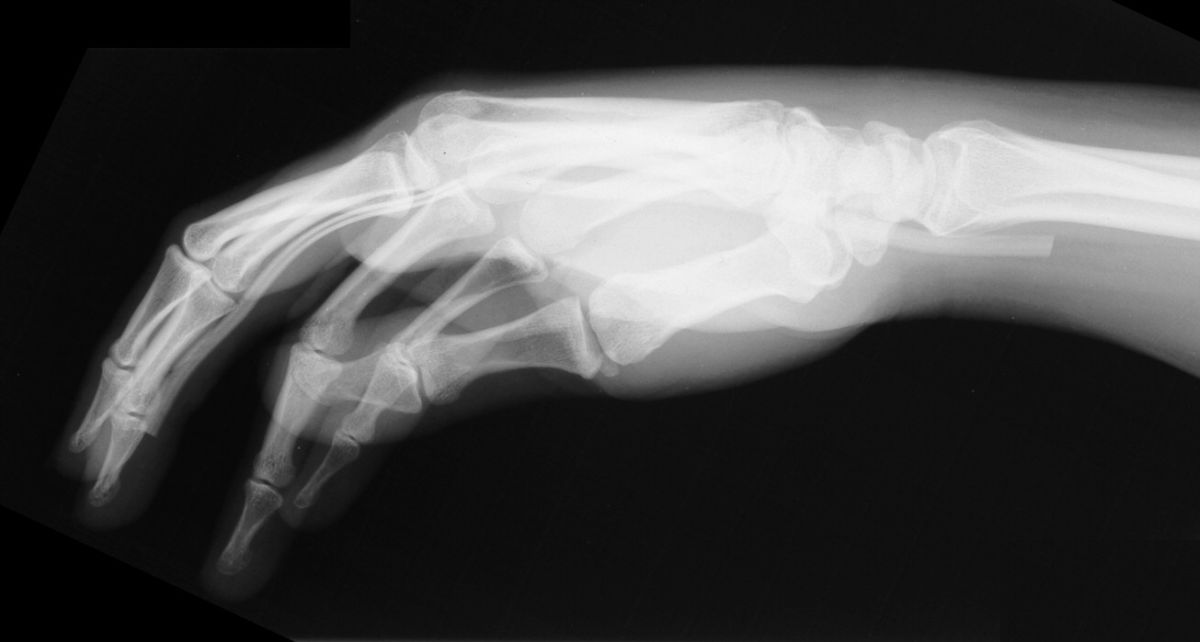

Radiographs demonstrating proper tendon spacer position and no bowstringing.